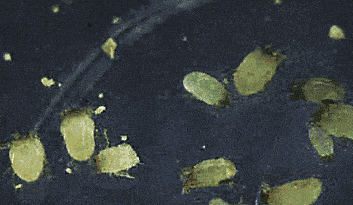

一、读懂听力检查报告孩子听力检查报告,林林总总不过是那么几样:声阻抗、听觉脑干电位ABR、多频稳态ASSR、(颞骨)CT影响检查(显示中、内耳及内听道情况)等等。医院一般...